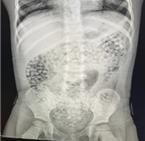

수분을 흡수해 팽창하는 속성이 있는 워터비즈가 체내에 유입되면 장 폐색 등 심각한 상해를 입을 수 있다는 경고다.

소비자원은 25일 최근 5년간 소비자위해감시시스템(CISS)에 워터비즈 관련 안전사고가 총 102건 접수됐다고 밝혔다. △2020년 17건 △2021년 23건 △2022년 29건 △2023년 23건 △2024년 10건 등 꾸준히 발생하는 추세로, 전부 만 14세 미만 어린이에게 발생했다.

활동 범위가 넓어지고 호기심, 탐색 욕구가 강해지는 '걸음마기(1~3세)' 사고가 해당 기간 전체 발생 건수의 67.6%를 차지했다. 대부분 가정에서 발생했으며, 워터비즈를 삼키거나(44.1%), 귀·코 등에 집어넣는 체내 삽입(54.9%)이 많았다. 어릴수록 삼킴 사고에 더 취약했다.

미국은 워터비즈를 완구·교구·기타 감각 도구 등 어린이용품으로 판매하지 못하게 하는 법안 도입을 추진 중이다. 2023년 7월 위스콘신주에서 10개월 영아가 워터비즈를 삼켜 장 폐색으로 사망한 사례가 보고된 데 따른 조치다. 당시 미국에선 워터비즈 안전사고가 6,000건 일어났다.